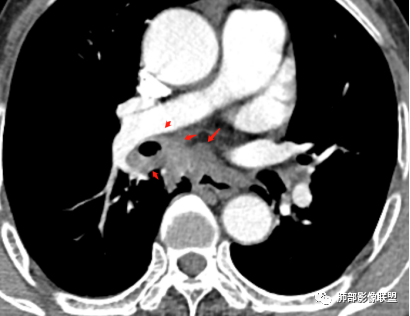

(1)病灶形态和分布:双肺散在点片影,可见树芽征。右肺下叶内基底段实性密度团块状影,底部坐落膈面、浅分叶,略呈圆锥形沿血管支气管束探及肺门,可疑“支气管爬行征”。奇食窝区分出子灶。病灶轻中度强化不均,斑片状低密度无强化区,疑坏死,未见钙化。右肺门及淋巴结肿大。

(2)支气管和血管:右肺支气管分支管壁弥漫性增厚,中间段支气管散在结节样凸起,右肺下叶内基底段支气管闭塞,但远端可疑复出。余病灶围绕支气管腔内远端无明显阻塞性不张。内部血管走形自然,提示包绕为主。